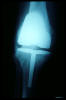

Prótesis completa de rodilla. Situación postquirúrgica.

Prótesis completa de rodilla. Situación postquirúrgica. Lateral.

Prótesis completa de rodilla.Lateral.

Prótesis completa de rodilla. Frontal.

Prótesis completa bilateral de rodillas.